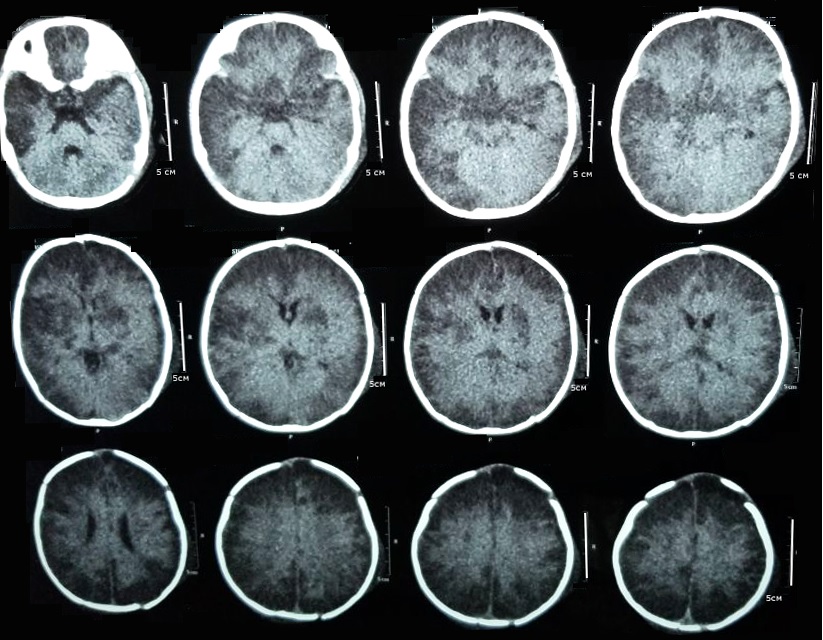

Complicated encephalitis in pediatrics: a case report

Marília Freitas Santana, Lara Moreira Ferreira, Gabriele Sousa Barbosa, Liane Carvalho de Brito de Souza, Carlos Eduardo Jucá, Washington Aspilicueta Pinto Filho

79-83